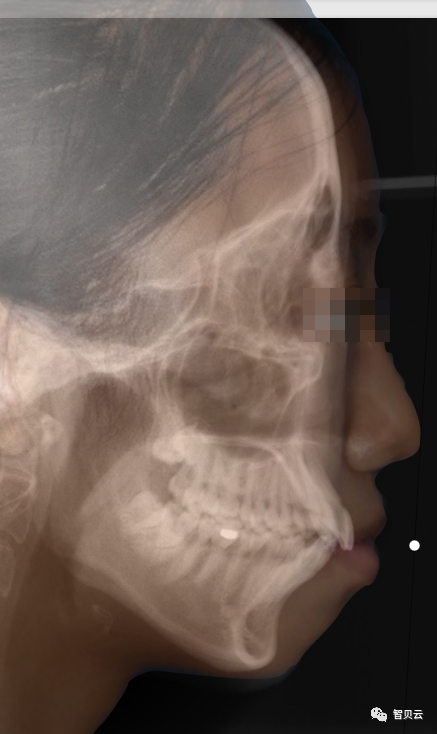

_PRE-TXNorm FMIA°47°55.0SNA°77.7°83.0SNB°70.2°80.0ANB°7.5°3.0FMA° 29.826PFH/AFH70.5°70Z Angle°50.3°77U1-FH113.0110.0IMPA°103.297.0U Lip to s’ line6.3 mm5.0L Lip to s’ line3.9 mm3.0OP-FH1215

头侧位片:

▲下颌后缩,骨性Ⅱ类

▲高角,颏部发育不足

▲上下前牙唇倾

Post-TXPRE-TXPost-TXNormFMIA°47°57.555.0SNA°77.7°76.883.0SNB°70.2°73.780.0ANB°7.5°3.13.0FMA° 29.828.026PFH/AFH70.5°65.970Z Angle°50.3°64.477U1-FH113.0103.7110.0 IMPA°103.291.197.0U Lip tos’ line6.3 mm3.25.0L Lip to s’ line3.9 mm1.03.0OP-FH1212.615

牙根基本平行,未见牙根吸收